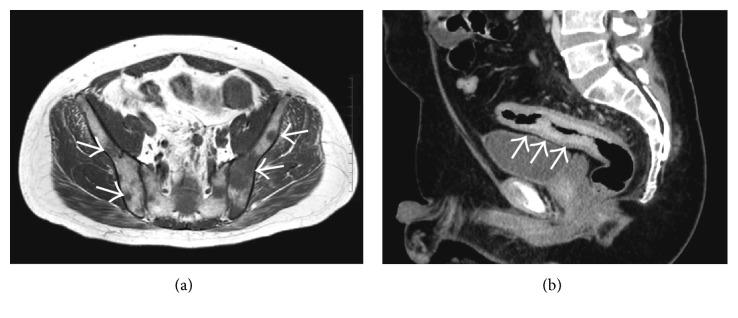

A 46-year-old man with severe back pain visited our hospital. Magnetic resonance imaging revealed extensive bone metastasis and rectal wall thickness. Colonoscopy revealed circumferential stenosis with edematous mucosa, suggesting colon cancer. However, histological findings of biopsy specimens revealed inflammatory cells but no malignant cells. The patient underwent endoscopic ultrasound, which demonstrated edematous wall thickness without destruction of the normal layer structure. After unsuccessful detection of neoplastic cells by boring biopsies, we performed endoscopic mucosal resection followed by boring biopsies that finally revealed signet ring cell carcinoma. Herein, we present a case and provide a review of the literature.

一名46岁的严重背痛男子前来我院就诊。磁共振成像显示广泛的骨转移和直肠壁增厚。结肠镜检查发现环形狭窄,黏膜水肿,提示结肠癌。然而,活检标本的组织学检查结果显示有炎性细胞,但无恶性细胞。患者接受了内镜超声检查,显示肠壁增厚且水肿,但正常层结构未被破坏。在通过钻取活检未能检测到肿瘤细胞后,我们进行了内镜黏膜切除术,随后再次进行钻取活检,最终发现印戒细胞癌。在此,我们报告一例病例并对相关文献进行综述。